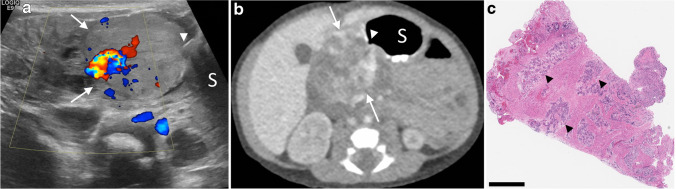

Fig. 10.

Gastric outlet obstruction caused by congenital duodenal hemangioma in a 5-day-old girl. a, b Transverse color Doppler US (a) and axial contrast-enhanced CT (b) images demonstrate a predominantly solid vascular mass (arrows) in the right upper quadrant directly adjacent to the stomach (S), with interrupted peripheral enhancement on CT. Air within the lumen of the gastric outlet is visible coursing into the mass (arrowhead), indicating gastrointestinal origin. c Hematoxylin and eosin stain of the resected mass (bar=800 μm) shows tufts of capillaries infiltrating the muscularis propria (arrowheads). GLUT1 stain was negative in these capillaries (not shown), excluding infantile hemangioma and confirming congenital hemangioma